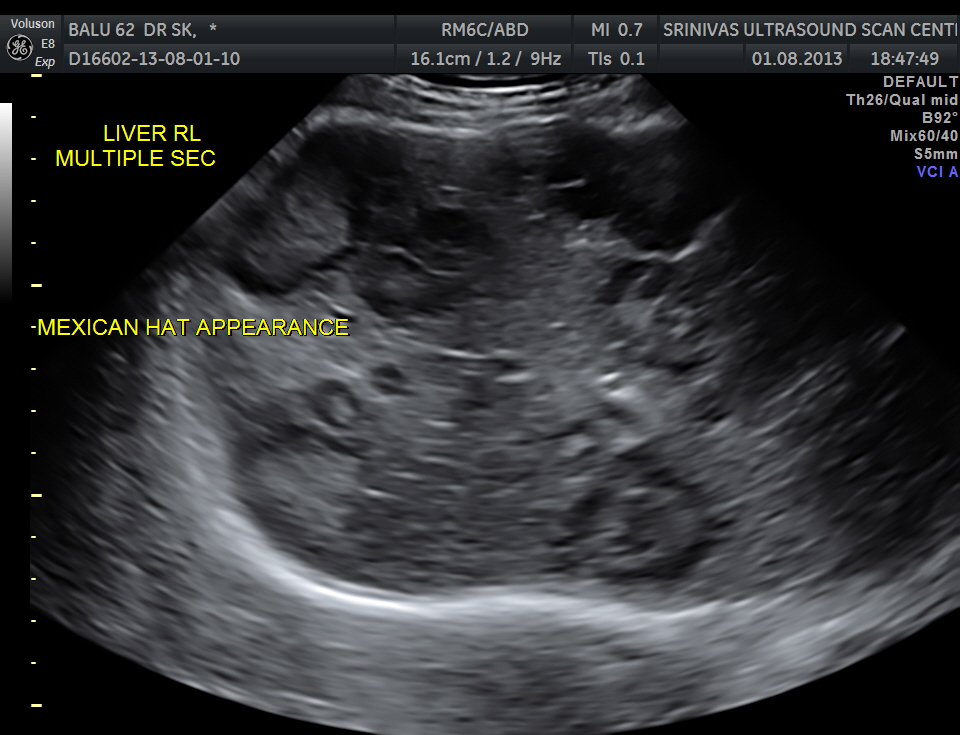

His liver showed multiple secondaries .

secondaries show target appearance or bird’s eye view of mexican hat appearance

DISCUSSION : Generally the target sign or the bird’s eye view of the Mexican hat sign could signify colo-rectal carcinoma.